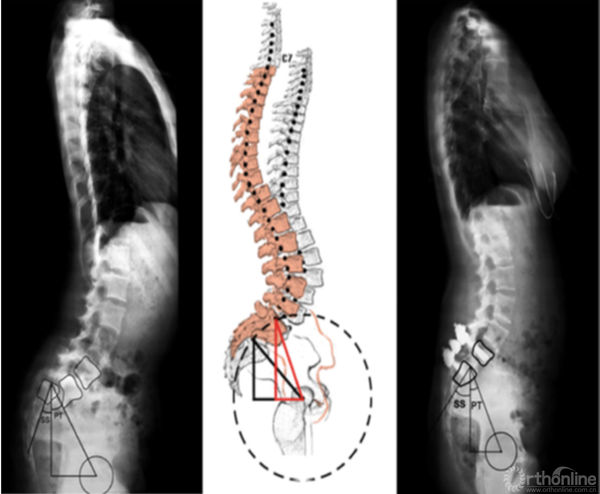

2. 骶骨形态不规则

骶骨形态不规则,通常是由于力学因素造成的。2012年,Sevrain[7]根据PI值将滑脱分为低PI组和高PI组,生物力学测试结果表明,低PI组人体重心位于骶骨中后区,而高PI组重心则分布在骶骨前方。从而更容易造成骶骨形态发生轻度或中度形态变化,L5椎体出现相应梯形变,从而亦会造成滑脱进展。